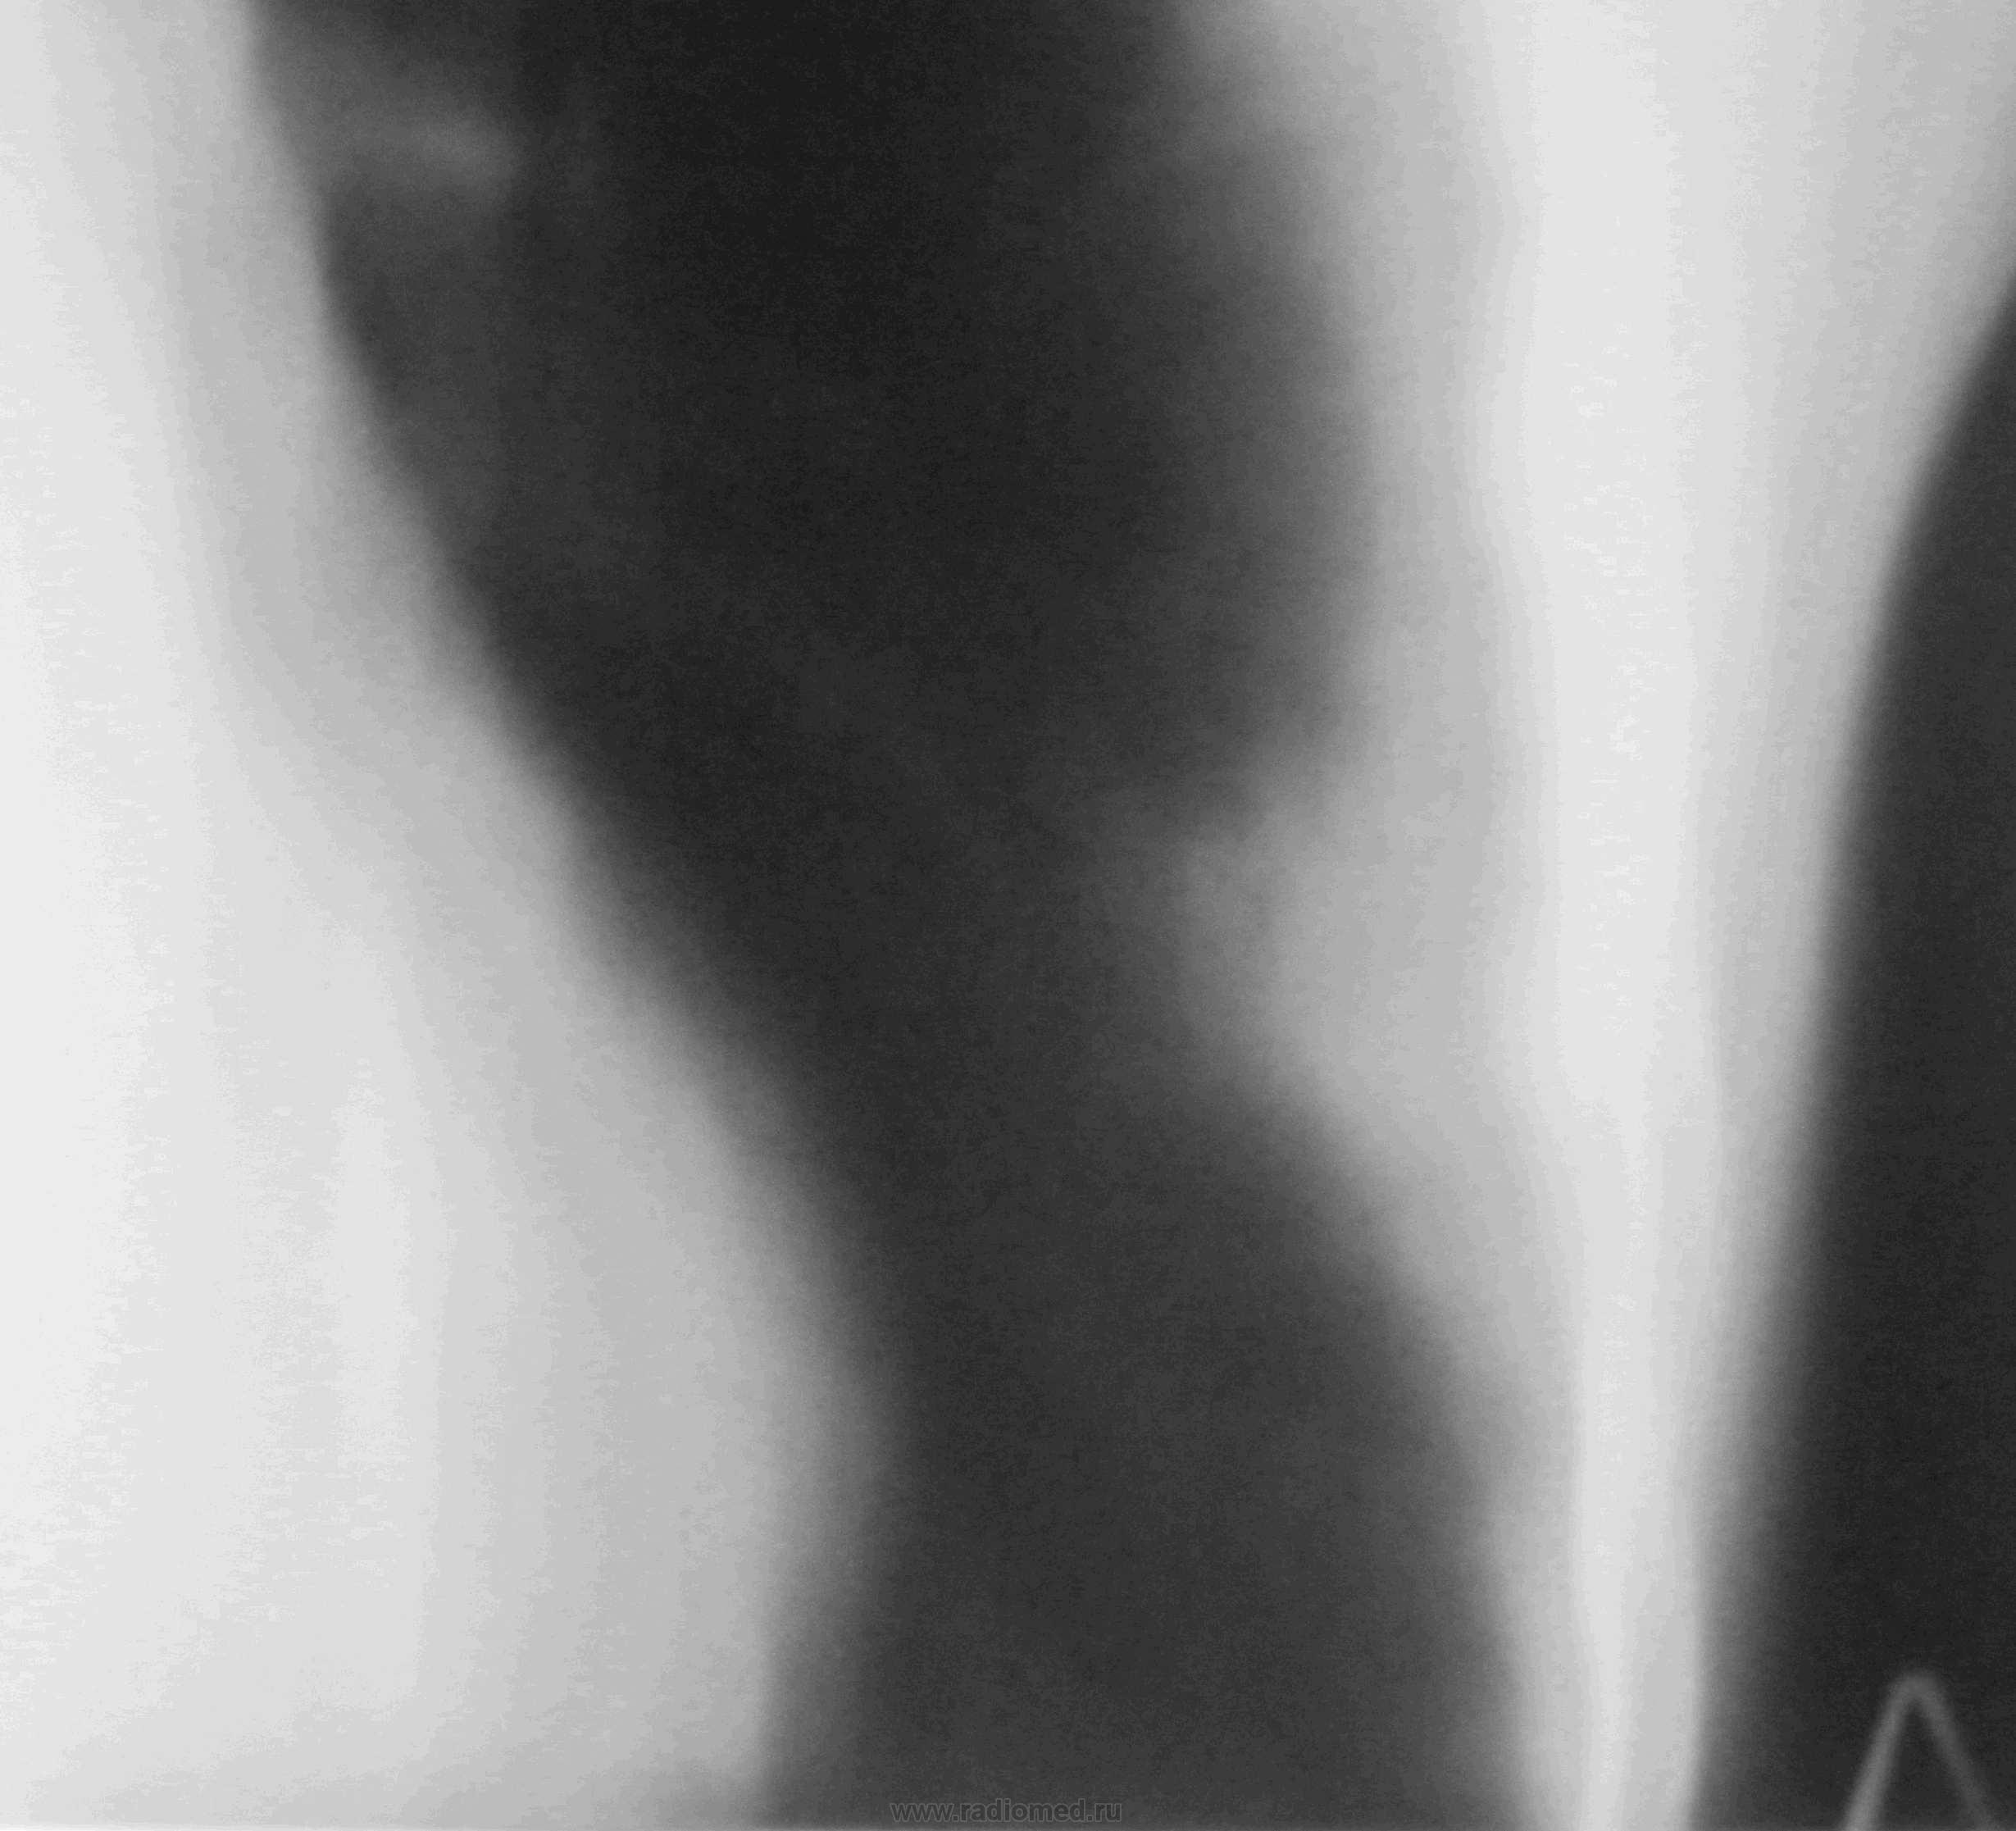

Интересно, какие мысли будут по поводу этой "блямбы"

img_0132._boyamba.jpg

Молодому человеку 20 лет. Снимки разместил по порядку с периодичностью в неделю. С момента поступления прошло полтора месяца. За это время, после инфекционного отделения, лечился в туберкулёзном, а после в пульмонологии (до настоящего времени).Последние рентгенограммы сделаны 2,04., а томограммы 4.04. По поводу кругляшки, особенно после туб.отд., думаю, что может выскочить и ТБЦ. Такое уже было, правда там был распад.

Левосторонняя S4-S5 пневмония, осложненная абсцедированием.По пятому по счету снимку явно на фоне инфильтрации видны зоны распада.А впоследствии и абсцесс сформировался-ТМГ тому подтверждение.Отдавайте торакалистам .